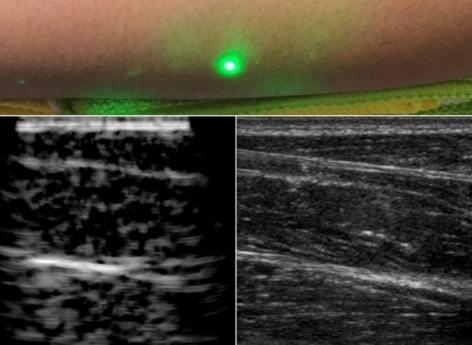

Dans le détail, le laser d'émission envoie une impulsion lumineuse qui est rapidement absorbée par la peau et convertie en ondes sonores par l'effet photo-acoustique, c’est-à-dire la génération de son par la lumière. Les ondes sonores générées interagissent avec des tissus identiques aux ultrasons conventionnels et les signaux réfléchis sont détectés par un interféromètre laser à la surface de la peau. Les lasers sont ensuite déplacés sur la surface de la peau pour produire une image.

Testé avec succès sur des sujets humains, ce système a montré que les ultrasons laser sont sensibles aux mêmes caractéristiques des tissus que ceux détectés par les ultrasons conventionnels. Il permet par ailleurs d'obtenir des images à des profondeurs de l'ordre du centimètre, ce qui est beaucoup plus profond que les autres techniques d'ultrasons optiques et est comparable aux profondeurs d'imagerie des ultrasons cliniques modernes.